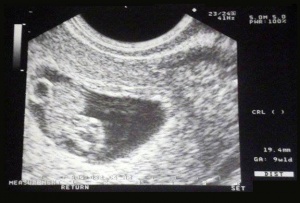

Ugyancsak szerdára volt időpontom a 18. heti ultrahangra, eszembe is jutott, hogy be kellene telefonáljak, hogy biztosan mehetek, biztosan ma?! De úgy gondoltam, ennyire nem lehetek peches, így elindultam. Szerencsére tárt karokkal fogadtak, Luca köszöni szépen, tökéletesen jól van, ismét végig mozgolódott. A kedves doktorbácsi volt megint, aki 12 hetesen is nézte. Ja, és még mindig kislány, valószínű már így is marad!